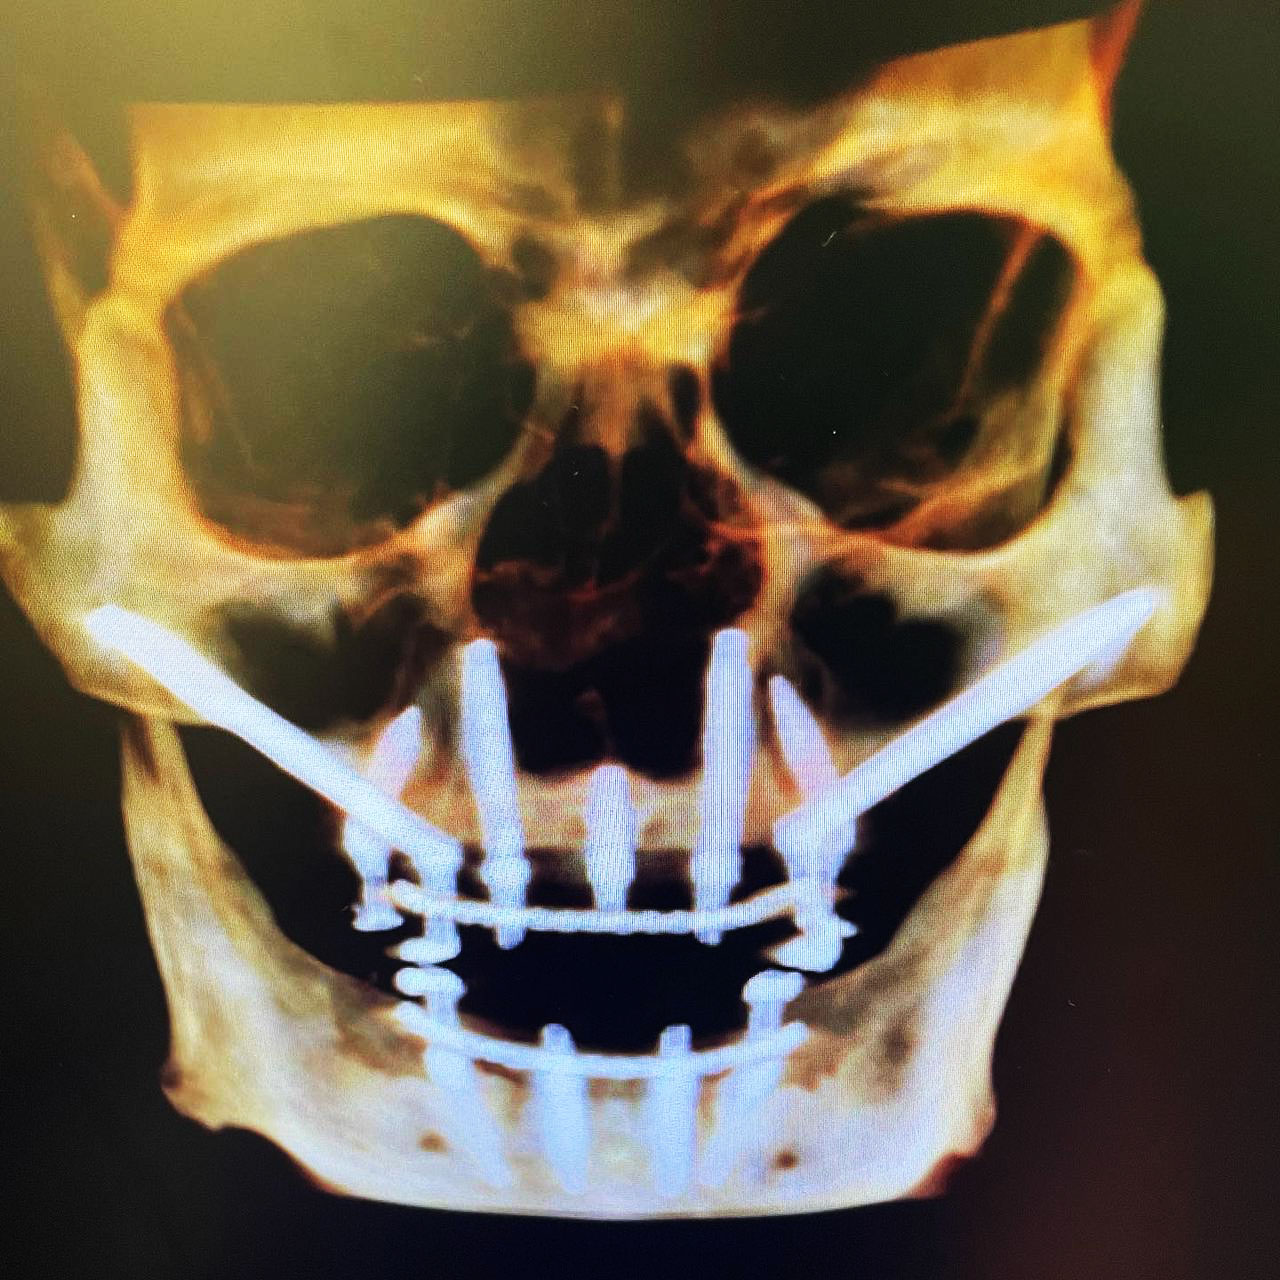

Quad Zygomatic Implants . This approach is used as the first line of treatment or as a rescue solution for failed implants and severe bone loss. Four zygomatic implants may be used in patients with severe maxillary atrophy for rehabilitation with a fixed or removable prosthesis. The “quad zygoma” concept involves the insertion of four zygomatic implants, with adequate anteroposterior spread and correct. Four zygomatic implants (quad zygoma) can be used in patients with severe maxillary atrophy as an alternative to bone grafting to reconstruct the maxilla. The article describes the surgical. The aim of this study was to systematically review and compare the survival rates (srs) of oral rehabilitations performed with 2 zygomatic implants (zis) combined with. Adequate implant stability allows immediate rehabilitation with a fixed bridge or an overdenture. Quad zygomatic implants inserted in patients with severely atrophic edentulous maxillae have a high implant survival rate, but the incidence of.

Four zygomatic implants (quad zygoma) can be used in patients with severe maxillary atrophy as an alternative to bone grafting to reconstruct the maxilla. The “quad zygoma” concept involves the insertion of four zygomatic implants, with adequate anteroposterior spread and correct. This approach is used as the first line of treatment or as a rescue solution for failed implants and severe bone loss. Four zygomatic implants may be used in patients with severe maxillary atrophy for rehabilitation with a fixed or removable prosthesis. The article describes the surgical. The aim of this study was to systematically review and compare the survival rates (srs) of oral rehabilitations performed with 2 zygomatic implants (zis) combined with. Adequate implant stability allows immediate rehabilitation with a fixed bridge or an overdenture. Quad zygomatic implants inserted in patients with severely atrophic edentulous maxillae have a high implant survival rate, but the incidence of.

Quad Zygomatic Implants Adequate implant stability allows immediate rehabilitation with a fixed bridge or an overdenture. Quad zygomatic implants inserted in patients with severely atrophic edentulous maxillae have a high implant survival rate, but the incidence of. Adequate implant stability allows immediate rehabilitation with a fixed bridge or an overdenture. This approach is used as the first line of treatment or as a rescue solution for failed implants and severe bone loss. Four zygomatic implants (quad zygoma) can be used in patients with severe maxillary atrophy as an alternative to bone grafting to reconstruct the maxilla. The article describes the surgical. The “quad zygoma” concept involves the insertion of four zygomatic implants, with adequate anteroposterior spread and correct. Four zygomatic implants may be used in patients with severe maxillary atrophy for rehabilitation with a fixed or removable prosthesis. The aim of this study was to systematically review and compare the survival rates (srs) of oral rehabilitations performed with 2 zygomatic implants (zis) combined with.